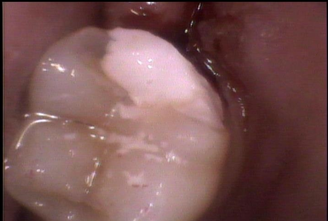

After

| 処置内容 | 親知らずの抜歯後、歯茎より下に部分にフィットするセラミックを入れる治療 |

| 備考 | 銀歯による修復は素材の身体への害はもちろんのことせっかく治療した歯が再度虫歯になってしまう可能性があります。 セラミックを使う事でより歯を歯周病や虫歯から長持ちさせることに役立ちます |